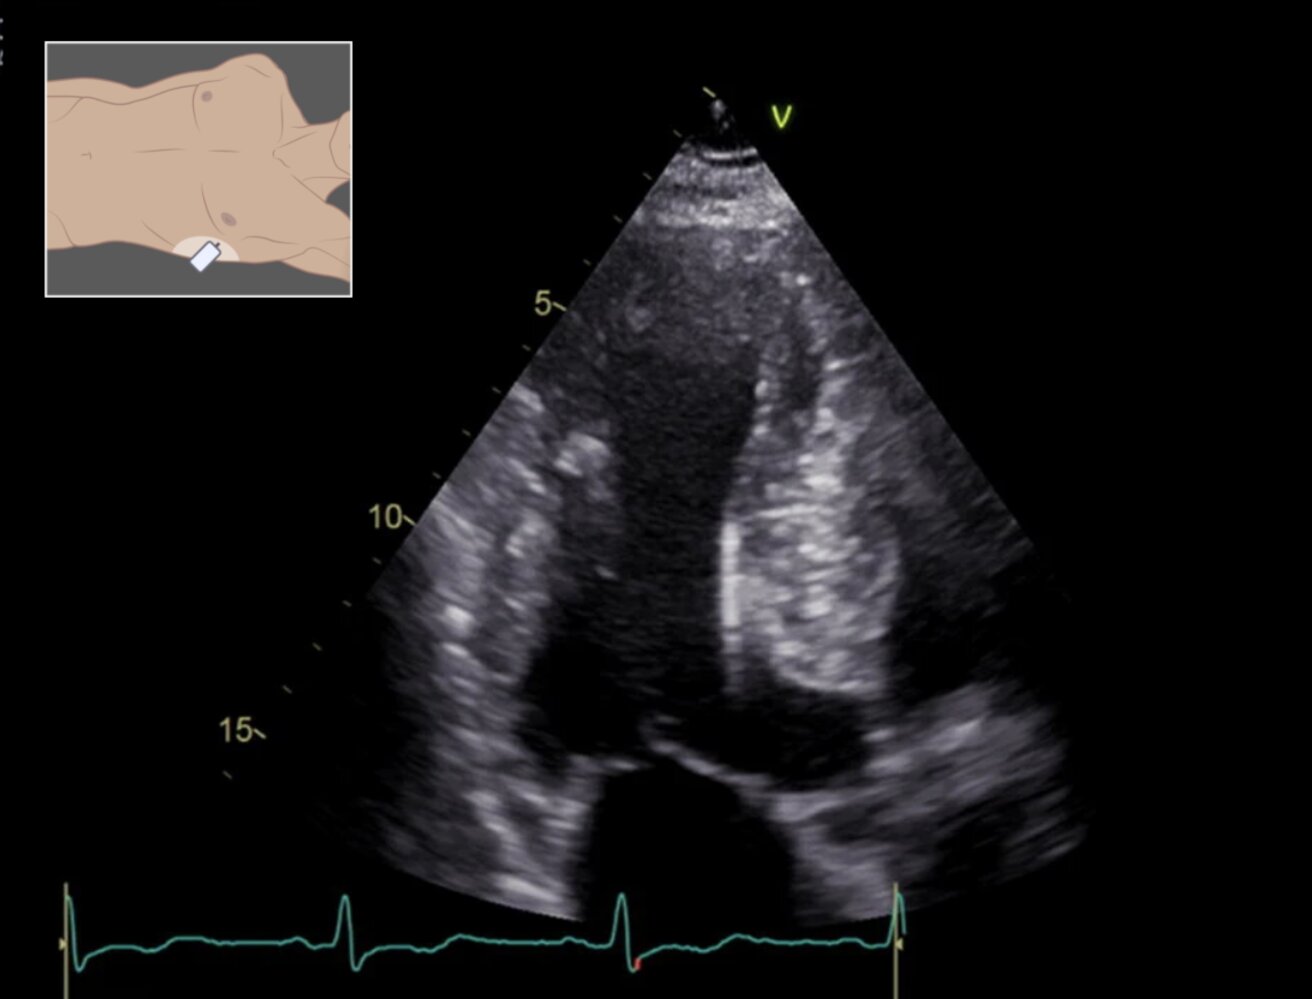

• Echocardiography and cardiac MRI

• RV enlargement

• RV wall motion abnormalities

• ↓ RV EF

• Localized RV aneurysms